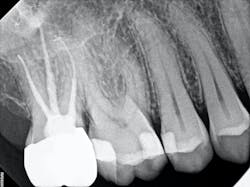

The iTero scanner was able to clearly define the delineation between the soft and hard tissue as can be seen in this image of the digital die trim (figure 3). Radiographs were captured on delivery revealing a clinically acceptable outcome for the patient (figure 4). Direct restorations were completed on teeth Nos. 3 and 4 during this visit.